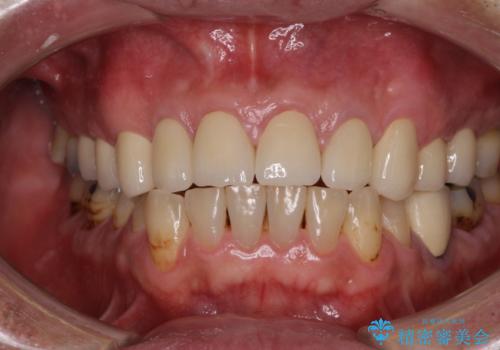

当初は前歯6歯をオールセラミッククラウンで補綴する予定でしたが、前歯が綺麗に仕上がったことで、奥歯まで延長して補綴することとしました。

黄ばんだ前歯や白すぎたクラウン、プラスチックの継ぎ接ぎなどを全てオールセラミッククラウンの統一感のある前歯に仕上げました。